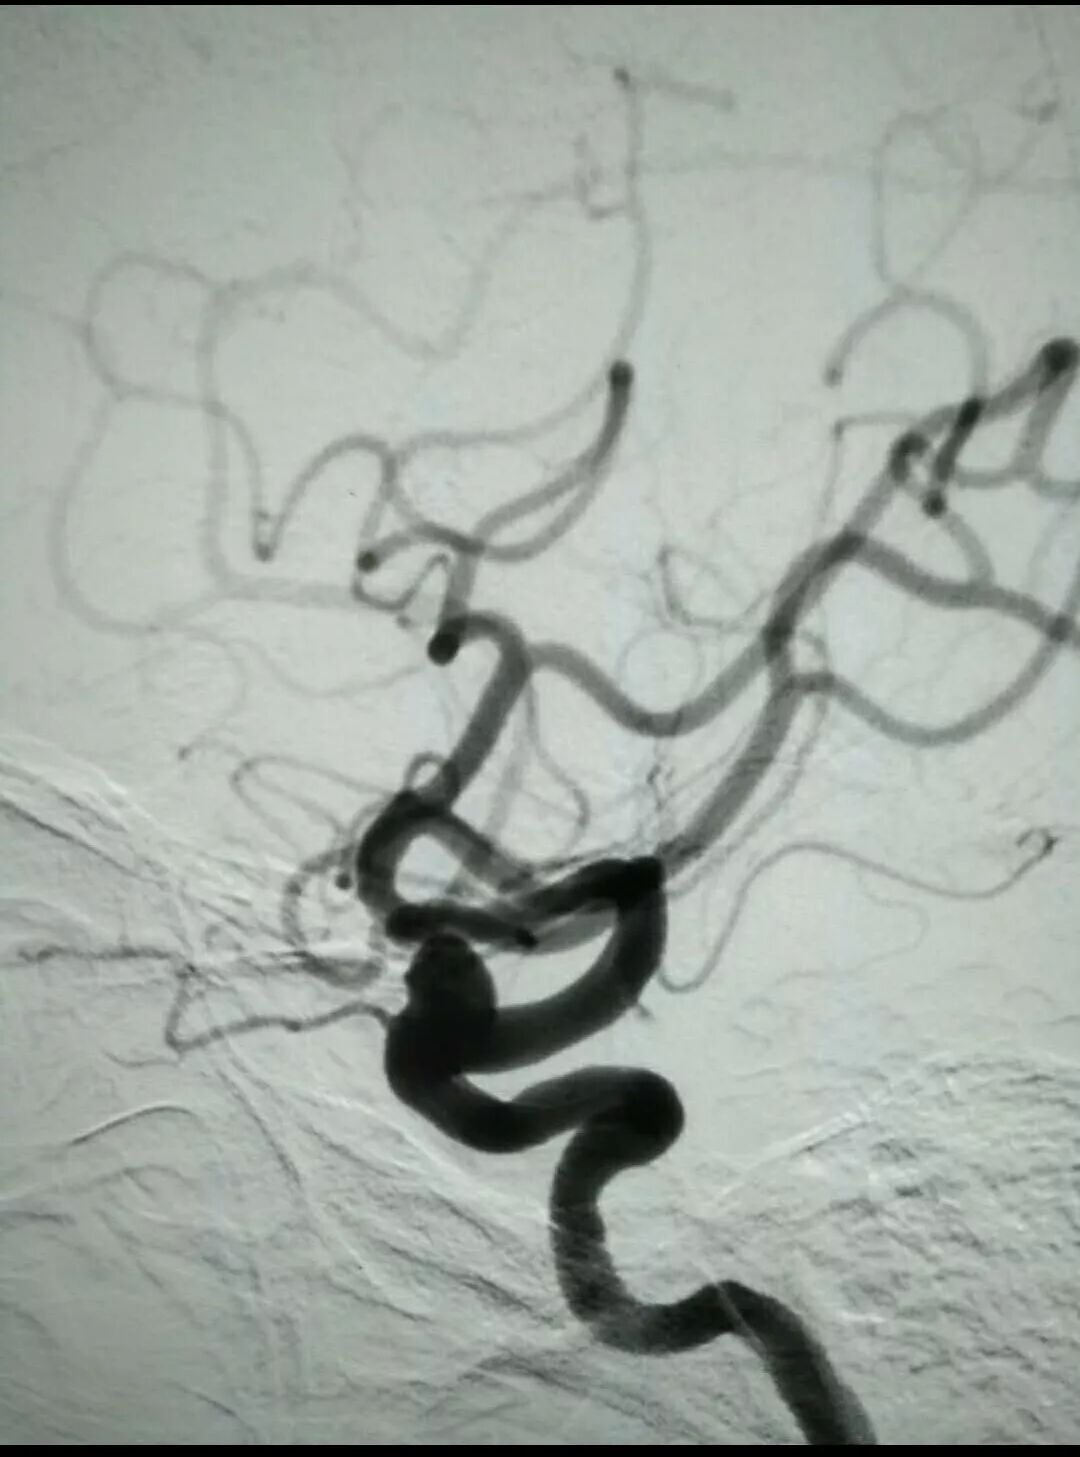

“医生、医生我时不时会头疼,快帮帮我。”2018年7月10日下午,一位44岁的女性患者带着磁共振片子来到我院求助。接诊的外科三病区医生胡要锋详细阅片后,MRA怀疑右侧颈内动脉虹吸段动脉瘤,联系科主任张兵杰,经全科综合考虑患者需行DSA检查进一步明确动脉瘤位置、形态、大小与载瘤动脉的关系。7月11日下午,DSA检查结果提示右侧颈内动脉眼段动脉瘤,约5mm*6mm大小,动脉瘤俗称为“脑内不定时炸弹”。

7月13日中午,在我院实行神经介入微创手术,诱导、插管麻醉、穿刺、确定工作位、弹簧圈填塞,手术按部就班的进行。由于为宽颈动脉瘤,手术必须在支架辅助下进行,支架到位后小心释放,通过血管内途径在支架辅助下直接闭塞脑动脉瘤,从而达到拆除“炸弹”的目的。